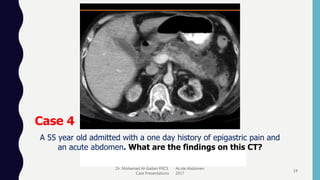

Case 4

A 55 year old admitted with a one day history of epigastric pain and

an acute abdomen. What are the findings on this CT?

Answer 4

Severe Necrotizing Pancreatitis

• Presents as Acute Abdomen

• Treatment is supportive

• Modified Glasgow scale:

• 3 or > Severe Pancreatitis (15% Mortality)  ITU

• Consider US percutaneous drainage for Abscess

• ERCP for impacted CBD stone

• Surgery: Necrosectomy, Emergency Cholecystectomy